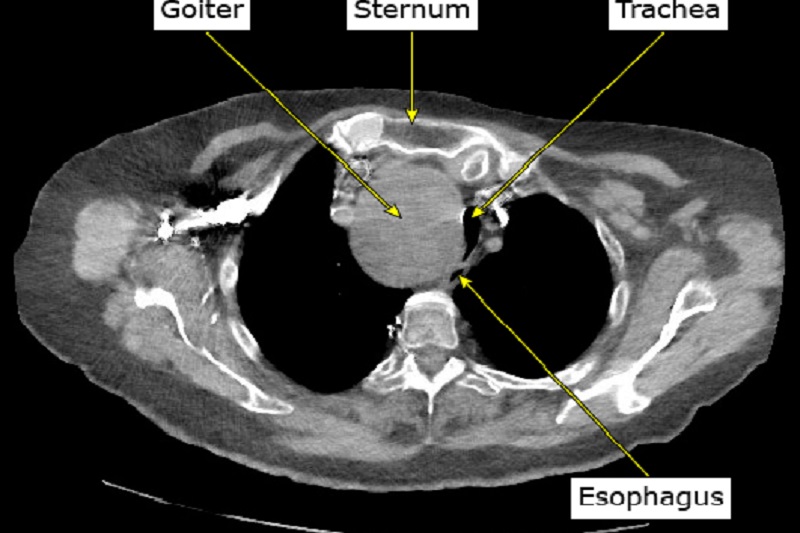

X - quang lồng ngực hoặc cắt lớp vi tính, cộng hưởng từ vùng ngực: được dùng trong trường hợp có nghi ngờ bướu giáp trong lồng ngực. X - quang có thể cho thấy có hay không bướu giáp trong lồng ngực và bướu giáp có chèn ép vào khí quản hay không. Còn để đánh giá mức độ bướu cổ cũng như ảnh hưởng của nó đến các cơ quan xung quanh, chụp cắt lớp vi tính hoặc cộng hưởng từ sẽ mang lại nhiều thông tin hữu ích hơn. Tuy nhiên cần lưu ý, các trường hợp bướu giáp, nếu chụp có tiêm thuốc cản quang cần được đánh giá và lưu ý kĩ, do trong thuốc cản quang có chứa một lượng lớn iod.

Hình ảnh bướu giáp trong lồng ngực chèn ép khí quản và thực quản